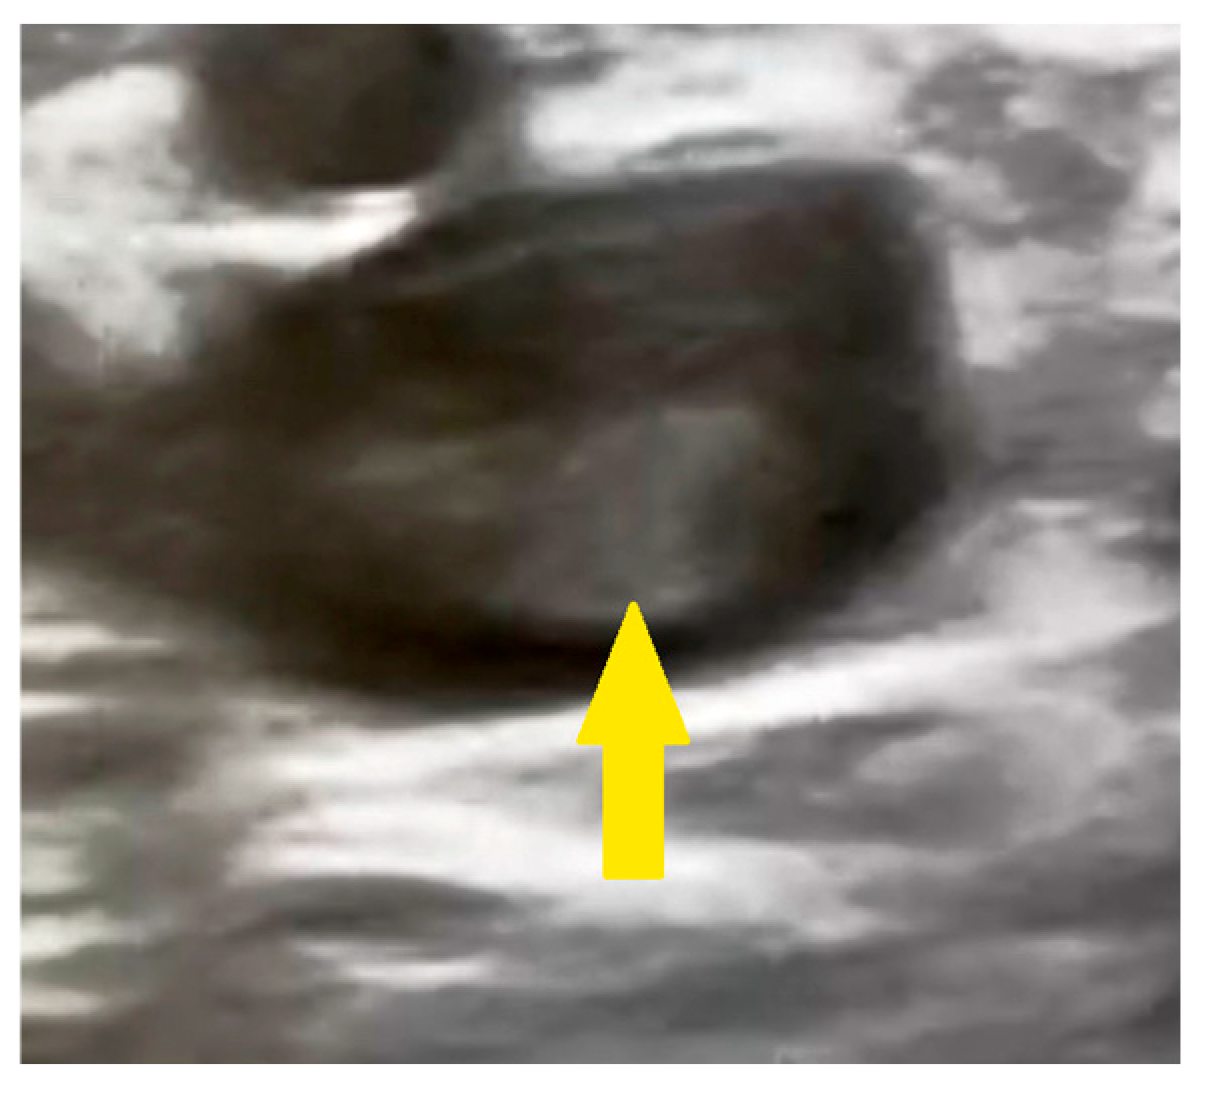

Further diagnostic workup included echocardiography, which revealed a dilated right ventricle measured at 36 mm in the parasternal long-axis view (normal range: 20–30 mm) (Figure 2A), moderate-to-severe tricuspid regurgitation, and a maximal tricuspid valve gradient of 51.6 mmHg measured by continuous-wave Doppler (normal: <10 mmHg) (Figure 2B).

Figure 2. (A,B) Echocardiography revealing a dilated right ventricle 36 mm in the parasternal long-axis view and a maximal tricuspid valve gradient of 51.6 mmHg measured by continuous wave Doppler (yellow arrows).